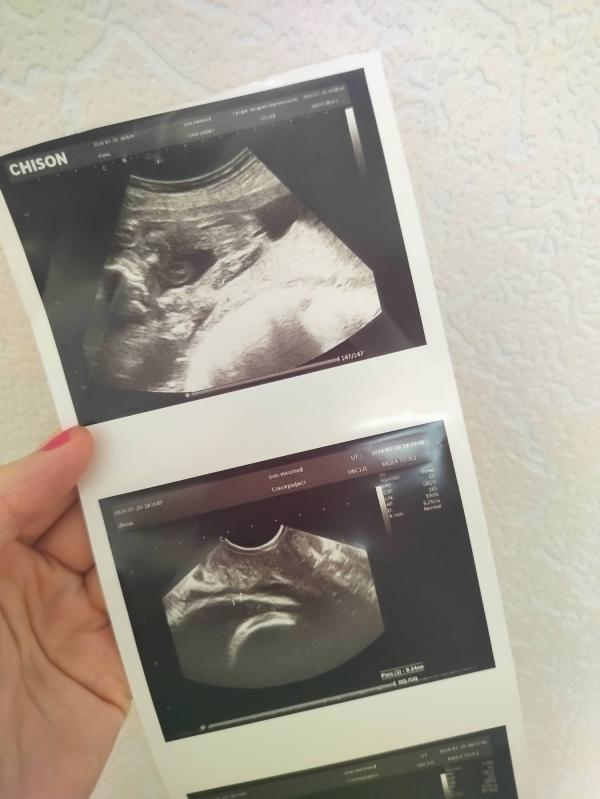

Кого ждать? Девочка или мальчик?

А вы кого увидели? девочку или мальчику?

Мне на 16 и 25 недели девочку 100℅

На 28 недели говорит типа похоже на мальчику может спутать с пуповиной или кому вообще верить? 🙂